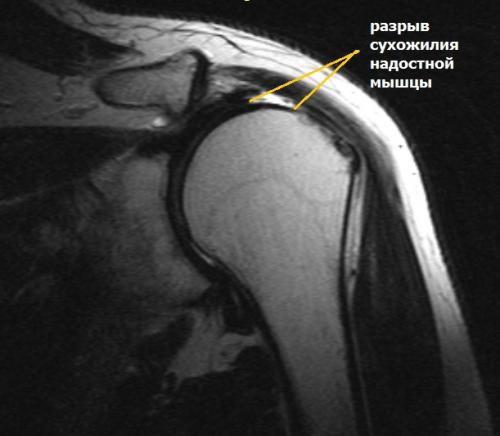

МРТ плечевого сустава. Корональные Т1-взвешенные МРТ. Переломы Хилла-Сакса и Банкарта.

Разрыв вращательной манжеты – также характерное повреждение области плеча – может быть связан как с травмой, так и дегенеративными процессами. Разрывы вращательной манжеты бывают полные и неполные. Кроме того, по МРТ плечевого сустава выделяют 3 градации, в основе которых лежит не только изменение сигнала на Т2-зависимых томограммах, но и морфологические изменения сухожилия.

МРТ. Корональная Т2-зависимая томограмма с подавлением сигнала от жира. Полный разрыв сухожилия надостной мышцы.